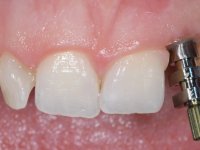

Before the treatment plan was elaborated, the patient was made aware of the inherent technical difficulty in aesthetical rehabilitation of the implant. After a long exchange of opinions with the dental technician, an unconventional treatment plan was presented, whose purpose was to minimize the aesthetic asymmetry between the left and right sides and between the cervical and incisal levels. The solution comprehended the realization of two veneers in composite resin of gingival tonality, to rehabilitate the interdental papillae of the edentulous space. A screwed abutment in Zr. with coronary and gingival component was planned for placement over the implant. As the implant angulation would put access to the screw on the vestibular face, confection of a feldspathic veneer was proposed, to be bonded to the abutment in order to camouflage the screw access hole. In tooth 1.2 a feldspathic veneer would be bonded, to correct microdontia and the small rotation.

An impression was made on the implant with open tray technique using soft and regular consistency putty. At the laboratory, after confection of the work model, a diagnostic waxing was performed, which sought to find an aesthetic compromise solution. In this sense, a temporary workpiece screwed onto the implant was used to simulate the difficulties we would have with screwing the definitive work. This study abutment consisted of wax to reproduce soft and hard tissues, seeking to anticipate the use of ceramics of gingival and coronary shade. Also, part of the interproximal papillae corresponding to the distal portion of the 2.1 tooth and the mesial tooth of the tooth 2.3 were also waxed, anticipating the use of composite resin “chips” with gingival tonality. Finally, a veneer was waxed to correct the microdontia of the tooth 1.2. In this waxing, the vestibular emergence of the orifice for access to the screw of the implant abutment was evident. Once this therapeutic option was accepted, the implant abutment in polymerized composite resin was prepared at the lab, as well as the papillary "chips", also in composite resin of gingival tonality. Tested in the mouth, the abutment was screwed and the "chips" bonded. The access hole of the screw was filled with composite resin. In subsequent consultation, a gingivectomy was performed on the cervical contour of teeth 1.3, 1.2 and 1.1 with the aim of correcting the asymmetry between the first and second quadrant. After the soft tissues were cicatrized, a dental bleaching was performed according to the patient’s aesthetic requirements. Final impression on the implant was made using the silicone open tray technique, taking care to individualize the transfer piece by copying the emergence profile of the patient’s provisional abutment. At the laboratory, the impression yielded a definitive working model, on which the abutment was waxed on a plastic insert. This process was carried out with the orientation of a wall of silicone based on diagnostic waxing. The wax made on the plastic part was placed in a special holder that allowed its scanning in a laboratory scanner. This scan by CAD process informed the design of an abutment in Zr. later materialized by a CAM process. The Zr. abutment was tested in the mouth, validating its clinical and imaging establishment. During this consultation, the choice of color was made by the ceramist, of both the coronary ceramics and the ceramic of gingival tonality to be used. Individualized color scales were used. At the laboratory, the coronary and gingival ceramics were placed on the implant abutment and later, on a working model with refractory gypsum, a veneer of feldspathic ceramic was made. This veneer was built on a surface specially designed for this purpose in the abutment. This surface tried to reproduce a dental preparation performed for the same effect. In the mouth the abutment was screwed with a torque of 35N, the access hole to the screw was filled with Teflon and later filled with composite resin. The veneer was bonded onto the implant abutment using the conventional bonding technique, with relative insulation. For economic reasons, the patient did not proceed to perform the veneer on tooth 1.2. Although a limited aesthetic compromise was expected from the outset, a result was achieved which satisfied the patient.